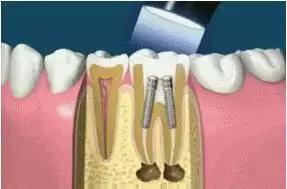

7、根管打桩:因牙体缺损过多,导致牙的强度(承受力量的性能)大幅度下降,不能很好地承受咀嚼力量。打桩的目的是增加牙根及牙冠的强度,增加患牙的稳固。